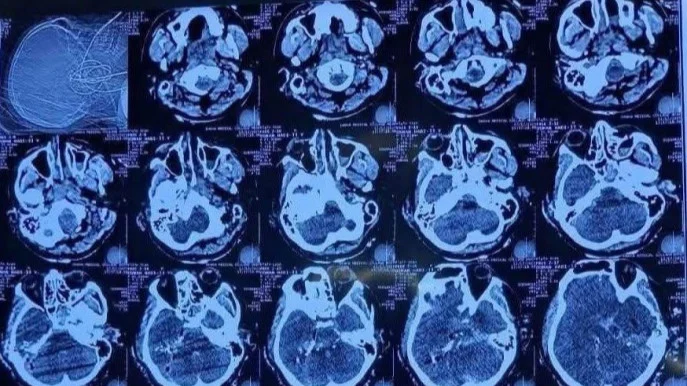

আঘাতের ভয়াবহতা বর্ণনা করতে গিয়ে ডা. সুমন রানা বলেন, ‘ব্রেনের আঘাতটা এমন ছিল যে, গুলি একদিক দিয়ে ঢুকে আরেকদিক দিয়ে বের হয়ে গেছে। যেদিক দিয়ে গুলি ঢুকেছে, অর্থাৎ কানের কাছের হাড়টি খুবই শক্ত। সেটি ভেঙে হাড়ের টুকরাগুলো মস্তিষ্কের ভেতরে ঢুকে আরও আঘাত সৃষ্টি করেছে, যাকে আমরা চিকিৎসার ভাষায় ‘সেকেন্ডারি প্রজেক্টাইল’ বলি। গুলিটি পেছন দিক দিয়ে ঢুকে মাথার অন্য পাশ দিয়ে বের হয়ে গেছে।’